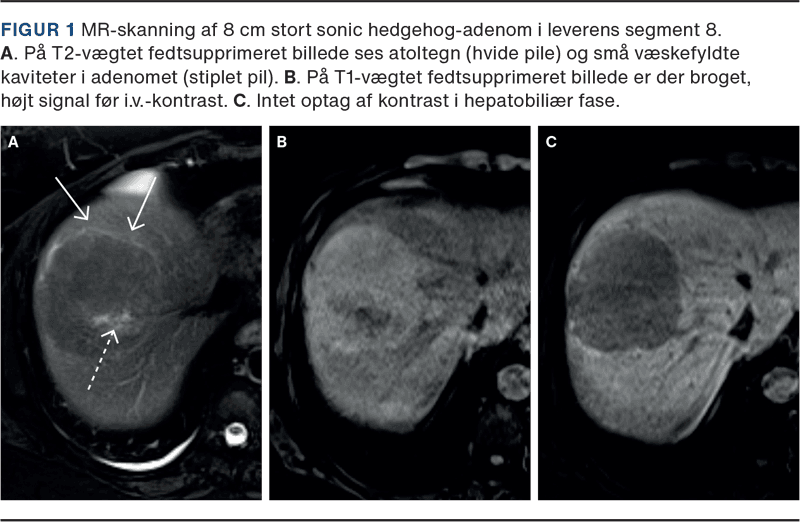

Sonic hedgehog-HCA (shHCA) kan ligne IHCA, men kan have mere specifikke fund såsom væskefyldte kaviteter (49%), blødningsfølger i form af fokalt højt T1- og T2-signal og nekroser (71%). Evt. optag af leverspecifik kontrast kendes ikke [21]. Eksempel ses i Figur 1.

Inflammatoriske HCA (IHCA) er markant hyperintense på T2-vægtede billeder og kan vise en accentueret hyperintens perifer ring (atoltegn). De fremstår ofte diffust hyperintense på T1-vægtede fedtsupprimerede billeder og kan have let broget fedtindhold. De viser kraftig arteriel opladning, som persisterer i venefase og senfase ved brug af ekstracellulær kontrast [17-19]. Mellem 14% og 29% optager leverspecifik kontrast [15, 17, 18]. Ved højt T1-signal før kontrast bør man sikre sig, at der er tale om reelt kontrastoptag i hepatobiliær fase ved hjælp af subtraktion.